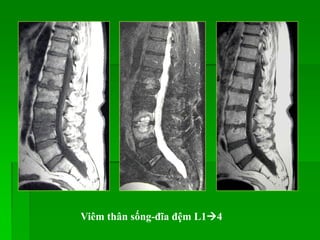

Viêm cột sống và đĩa đệm do vi trùng thường và do lao:

Viêm thân sống-đĩa đệm L14

Spondylodiskitis